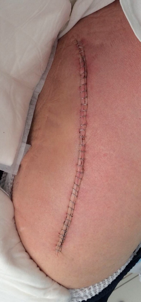

Post-Surgical Total Hip Removal and Replacement - Clinical Case

A 65 year old female with Lupus (controlled with chemotherapy) renal failure managed with dialysis at Mayo Clinic, Jacksonville, required the removal and replacement of a Stryker Total Hip Implant.

Day before and morning of surgery the surgical area was wetted with SilvaKlenz (left in place for 5 minutes) gently scrubbed with sterile gauze and rinsed with sterile water. The surgical area was then moistened with Silvion and lightly wrapped with sterile gauze. The surgical site was prepared according to hospital procedures at the time of surgery. After surgery, the incision was sprayed with Silvion. The day after surgery, and BID each day until the incision was healed, the incision site was cleaned with SilvaKlenz, rinsed, then moistened with Silvion. The contact bandage was lightly moistened with Silvion.